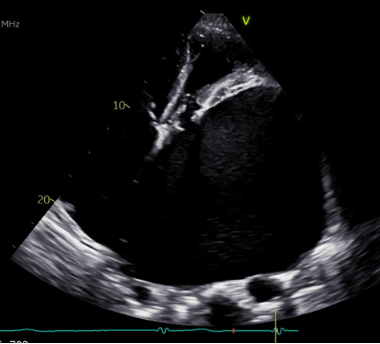

A 75-year-old man with permanent atrial fibrillation, previous mitral valve repair, and severe secondary TR was admitted with cardiac decompensation and symptomatic bradycardia. Echocardiography revealed extreme biatrial enlargement (left atrial volume 2755 mL, right atrial volume 557 mL) with compression of the right atrium and ventricle (Figure 1). Leadless pacing (Micra™, Medtronic) was chosen due to several reasons: the complex anatomy, high bleeding and infectious risk because of comorbidities and need for future surgical valve repair.

Figure 1:transthoracic echocardiography showing massive biatrial dilatation